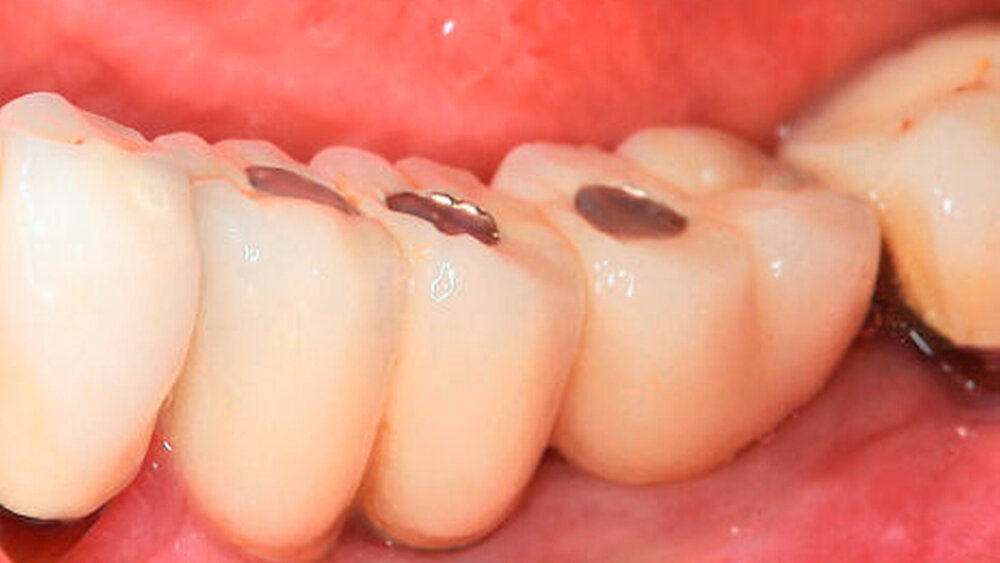

Bei einer jungen zahnlosen Patientin mit schmalem Alveolarkamm wurde klassisch präimplantologisch augmentiert (vestibulärer Knochenblock und BioOss-Anlagerung, Bio- Gide-Membran-Abdeckung) mit vier bis sechs Monaten Einheilzeit. ‧Unglücklicherweise entwickelte sie eine Wunddehiszenz mit ausbleibender Knochenregeneration und Verlust des Augmentats. Eine erneute Augmentation kam für sie wegen der OP-Belastung und einer sich weiter verlängernden Therapiedauer nicht infrage. Als eine mögliche alternative Versorgung stimmte sie der Insertion von drei Profile EV-Implantaten mit abgeschrägter Implantatschulter zu. Die Kontrolluntersuchungen nach zwei und fünf Jahren zeigten eine sehr gute Osseointegration und zudem eine sehr gute stabile periimplantäre Weichgewebssituation ohne zusätzliche peri‧implantäre Weichgewebsver‧dickung, ein Phänomen, so Wagner, das ein typischer Weichgewebevorteil für alle Implantate mit Platform Shift sei, nicht nur für das Profile EV. Als Hauptindikationen für diese anatomischen Implantatformen nannte Wagner